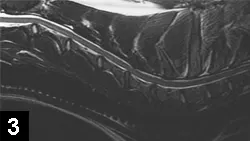

MRI of the cervical spine disclosed dorsal and ventral compression of the spinal cord at the level of the C5-C6 disk space (Figure 3).

Figure 3. Sagittal cervical spinal MRI showing dorsal and ventral compression of the spinal cord at the C5-C6 disk space.

The MRI results were consistent with dorsal and ventral compression resulting from disk-associated wobbler syndrome. In addition to a chronic type-2 disk herniation or protrusion, there was dorsal compression resulting from the dorsal vertebral laminae and hypertrophy of the interarcuate ligament. Disk disease was noted on MRI based on the decreased intensity of the C5-C6 and C6-C7 disks, indicating loss of water content.